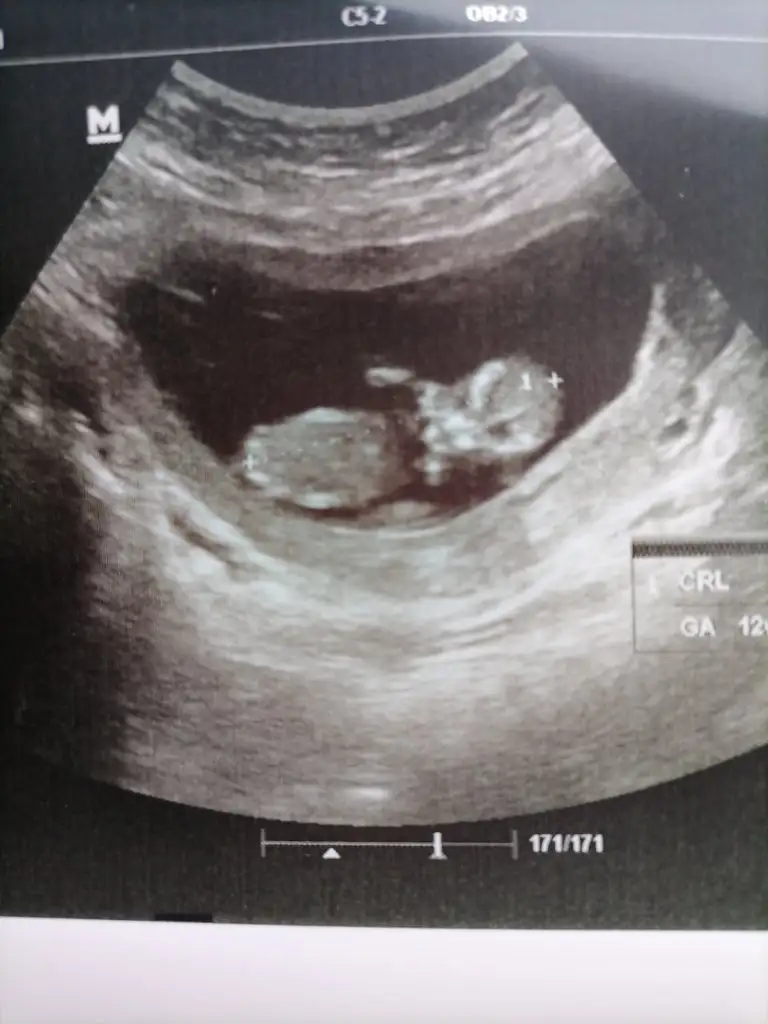

Ben öğrenmedim 30unda randevum var 12 haftalık olmuş oluyorum belki öğrenirim. Siz öğrendiniz mi?Bebeğin cinsiyetini öğrenen oldu mu acaba

Benimde suan 11 haftalık doktoruma 13 te öğreniriz dedi ama c tesi 11+3 kontrolum var belki ozman öğrenirmBen öğrenmedim 30unda randevum var 12 haftalık olmuş oluyorum belki öğrenirim. Siz öğrendiniz mi?

Erken gösteren de varmış geç gösteren de inş görürsün canımBenimde suan 11 haftalık doktoruma 13 te öğreniriz dedi ama c tesi 11+3 kontrolum var belki ozman öğrenirm

Ay caanım hiç anlamıyorum ben :) göstermiyor gibi ama :))Ultrasondan cinsiyet tahmini yapabilecek varmı

Çok iyi canım süper haber :) Kaç haftalık oldun şuan ?Selam kızlar bugün kontrolüm vardı 2 li tarama, ense kalınlığı burun kemiğine bakıldı hepsi iyi dedi doktorum. Ama cinsiyetimizi göremedik göstermedi

Canım şuan 11+6 ym ama ultrsnda 12+3Çok iyi canım süper haber :) Kaç haftalık oldun şuan ?

Bence kiz bugün bende kontrole gittim 11+3 kiz diye tahmin etti kesin olmamakla beraber görüntü böyleTahminlerini bekliyorum